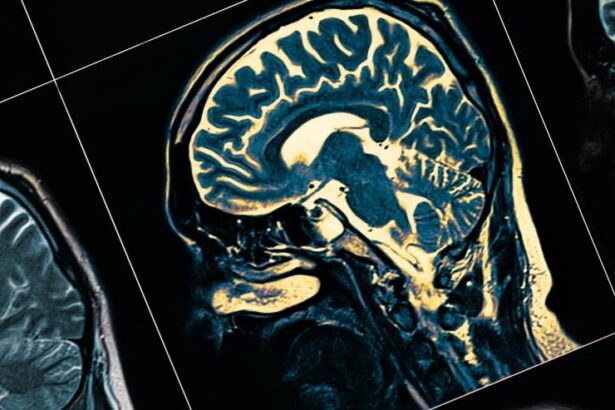

Thuốc Xanamem mở ra hy vọng cho các bệnh nhân Alzheimer. (Nguồn: heraldsun.com.au)

Các nhà nghiên cứu tại Linear – trung tâm nghiên cứu lâm sàng hàng đầu thế giới có trụ sở tại bang Tây Úc – đang tiến hành thử nghiệm một loại thuốc có thể điều trị bệnh suy giảm trí nhớ (Alzheimer), mở ra hy vọng cho hàng chục triệu người mắc bệnh này trên khắp thế giới.

Theo phóng viên TTXVN tại Úc, thuốc đang thử nghiệm này, có tên gọi là Xanamem, hoạt động bằng cách làm giảm lượng cortisol, loại hormone được sản sinh ra trong cơ thể khi một người bị căng thẳng.

Lượng cortisol trong nã o tăng cao có thể dẫn đến bệnh Alzheimer làm suy giảm trí nhớ và chức năng hành vi.